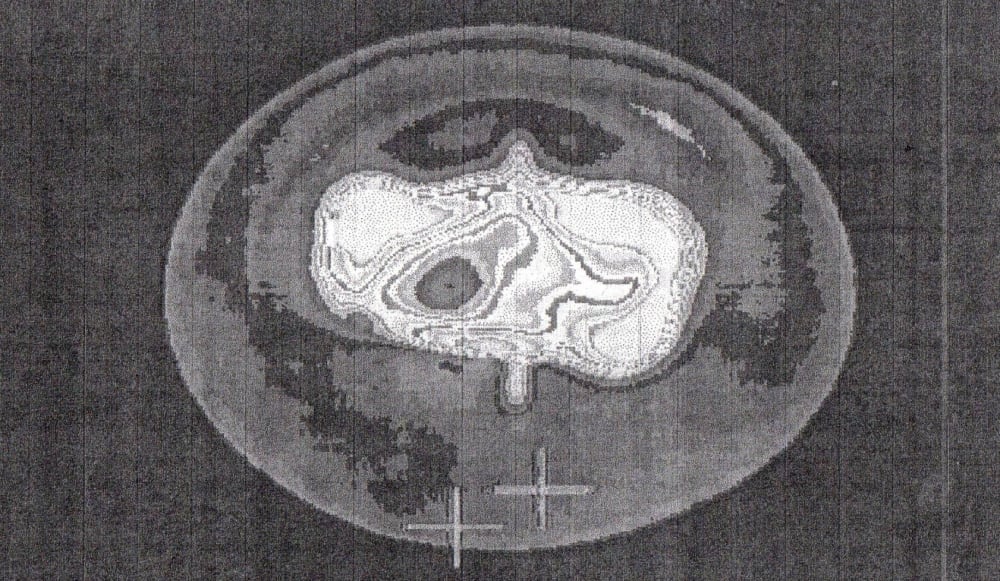

The result is a single, unified medical platform that delivers detailed, full-body images, on site.

This imager will be laptop-sized device. It will have roughly the same physical footprint as a laptop but at least twice the thickness in order to accommodate imaging components. The corresponding weight goal will therefore be approximately 5 lbs. The display is anticipated to be larger than an iPad but with the same image resolution as an iPad.